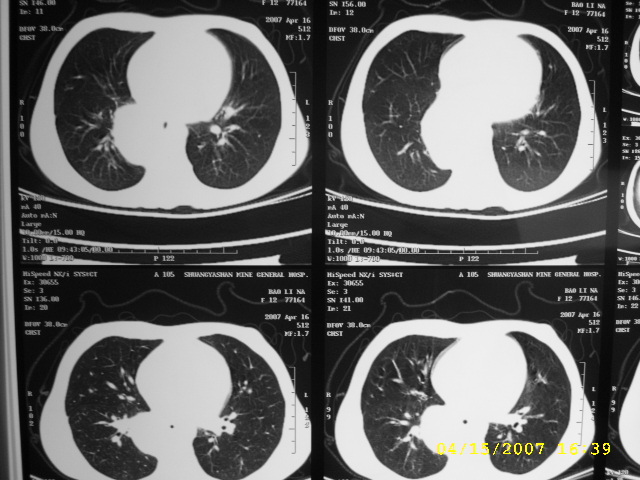

标题: PED0109:女,12,后纵隔占位十余年

女,12,后纵隔占位十余年。

女,12,后纵隔占位十余年,没什么特异性,考虑1纵隔囊肿2肺隔离症3神经源性肿瘤,建议增强